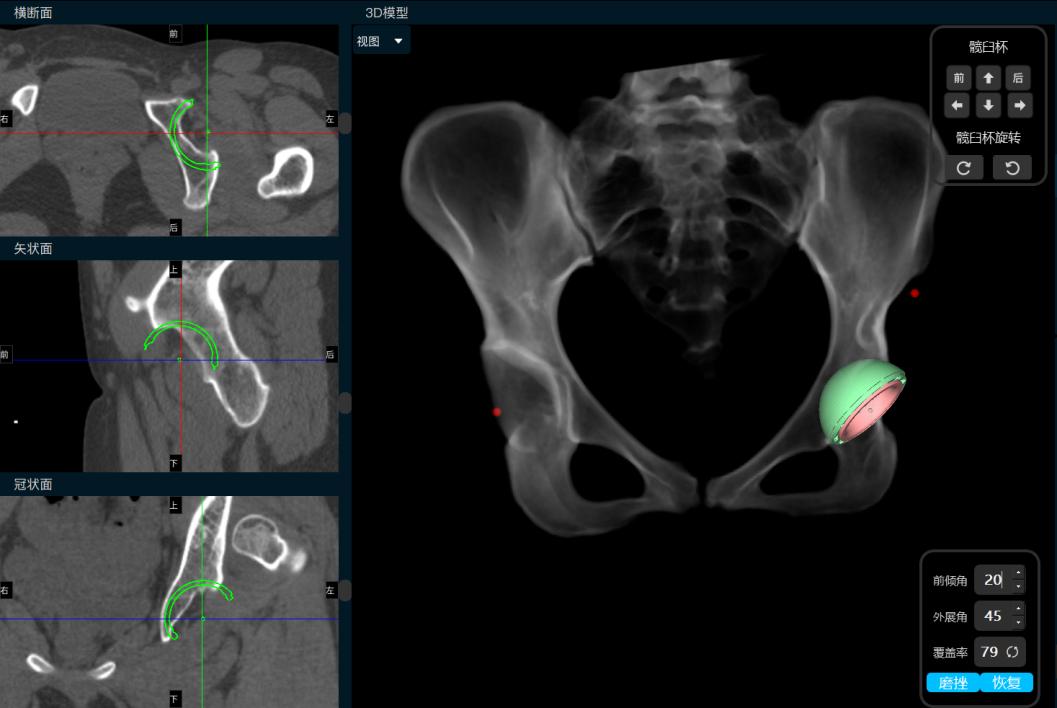

小张入院后,立即开始逐步进行相关检查,进行术前的准备。因为DDH的手术一般比较复杂,特别是这种脱位程度较高的患者,所以术前就需要更加精准的规划。对于小张的手术方法,耿硕副教授制定了两套方案:1.如果原来真臼内及股骨头的软骨条件良好并且相匹配的话,那么可以尝试将股骨头放进髋臼里配合骨盆截骨重建髋关节;2.如果软骨条件不好或难以匹配,那么只能行全髋关节置换术。但是所有手术方案都会有一个挑战,就是如果在安装完髋臼杯及股骨假体后复位时把股骨下拉过多,可能会造成神经等软组织的牵拉伤并且且因软组织张力过大可能造成假体松动,为了避免这种情况可能需要行股骨截骨减张,这样一期便不能恢复双下肢等长,需二期行骨延长术恢复下肢等长。在术前,为了适应软组织的张力状态及验证复位可能性,小张入院后即进行了患肢的牵引处置。为了精准的对手术做出规划,术前小张进行了下肢全长的三维CT扫描和模型重建,并且应用人工智能系统AI HIP对其进行术前手术方案的制定。人工智能能够利用患者的三维CT数据进行智能化识别解剖位点,匹配假体的大小及安放位置,通过对手术精准地预演,让外科医生在术前心中有数。通过人工智能系统的规划,计算出小张同学的双下肢腿长差和偏距差,计算出了旋转中心所需下移的距离和假体需要安放的位置等,髋关节置换方案为S-ROM假体系统,髋臼杯为PINNACLE 44号,内衬为BIOLOX28-44,因为患者比较年轻,所以选用了陶瓷对陶瓷的摩擦界面,能够实现更长的使用年限。根据术前规划数据,毕郑刚、耿硕团队提前准备了相应的假体和器械,为手术做了充分的准备。

人工智能术前规划